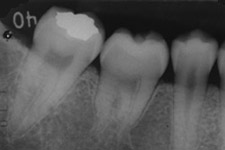

左:移植直後のエックス線写真。

右:移植後1ヶ月。